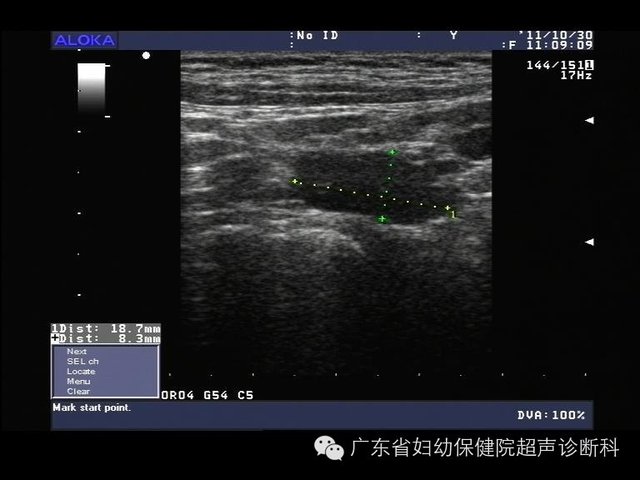

经皮超声造影检测兔VX2乳腺癌前哨淋巴结的引流路径观察

经皮超声造影检测兔VX2乳腺癌前哨淋巴结的实验研究.pdf张勇++王宗邦++杜丽丽【摘要】目的:观察采用经皮超声造影的方法检测兔VX2乳腺癌前哨淋巴结的引流路径并探讨其临床应用价值。方法:本实验选取的20只实验兔全部